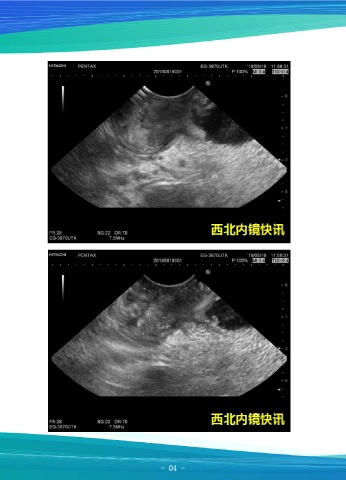

Page 4 - 西北内镜快讯8月刊